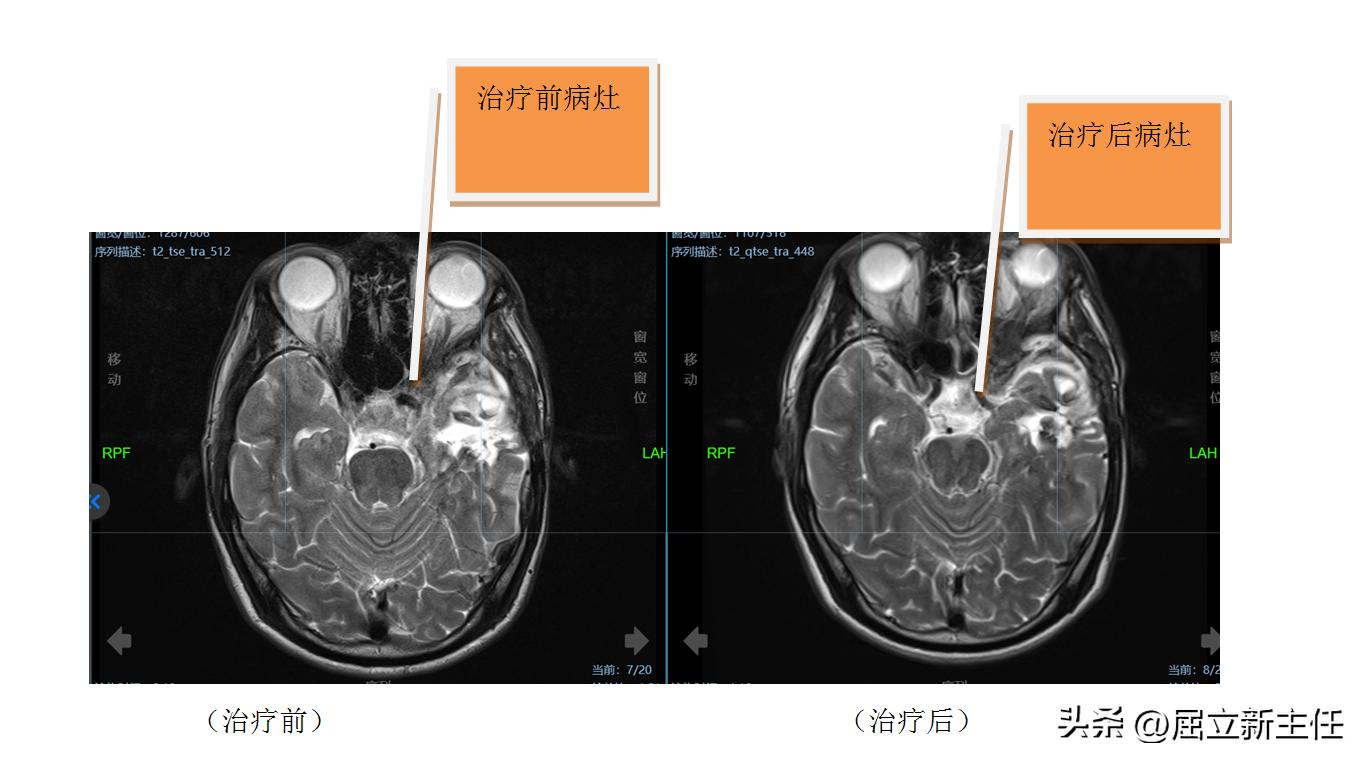

2022年8月20日, 陈昭入院广州中医药大学金沙洲医院肿瘤五科,屈立新教授看过他的病历又为他查体,诊断为“左侧中颅窝底沟通性脑膜瘤术后复发”。

8月21日,屈立新教授联合脑科、神经科、麻醉科会诊,最终为他制定了治疗方案:局部射波刀放疗。因为患者既往已行手术治疗,无法再次手术,经过射波刀放疗后可以提升生活质量,减轻患者的痛苦感。“虽然陈昭的病情比较棘手,但我们有信心帮他控制病情,然后联合中医药综合治疗,以此减轻放疗的副作用,抑制肿瘤进展”屈立新教授表示。

陈昭开始放疗后,屈立新教授又给予陈昭甘露醇+倍他米松脱水治疗,他的头晕、头疼都已经消失了,饮食与睡眠都良好,尤为关键的是他的左眼视力也有所恢复。这些症状的改善也给予他与病魔抗争的力量。